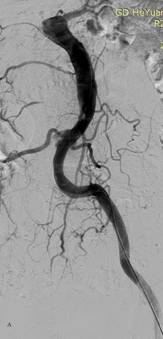

图2 患者男,57岁,胸腹痛7小时急诊入院,诊断为主动脉夹层(Standford B型),入院1周后行主动脉夹层腔内修复术,术后10天临床治愈出院。A为治疗前造影,B为覆膜支架修复破裂口后。